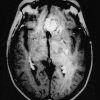

The company has captured 510(k) clearance for artificial intelligence-based software that facilitates brain and prostate image interpretations.